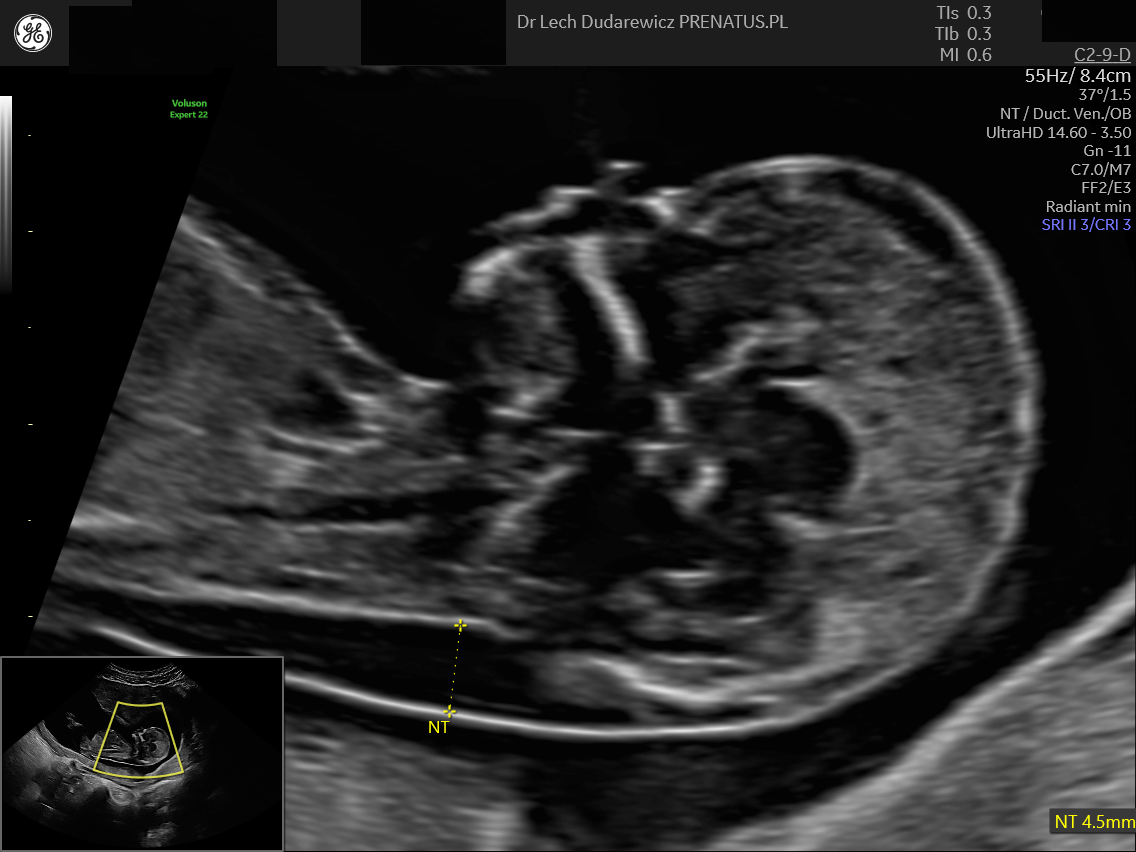

Zwiększona przezierność karkowa – czy to wyrok? Spojrzenie eksperta

Moment, w którym przyszła mama słyszy w gabinecie lekarskim:„u płodu widoczna jest zwiększona przezierność karkowa”,często jest jednym z najbardziej stresujących w całej ciąży. W jednej chwili radość ustępuje miejsca lękowi, a w głowie pojawia się tysiąc pytań:Czy moje dziecko jest chore?Czy zwiększona przezierność karkowa (NT) oznacza wadę genetyczną? Dziś chcemy odczarować ten parametr i wyjaśnić, […]